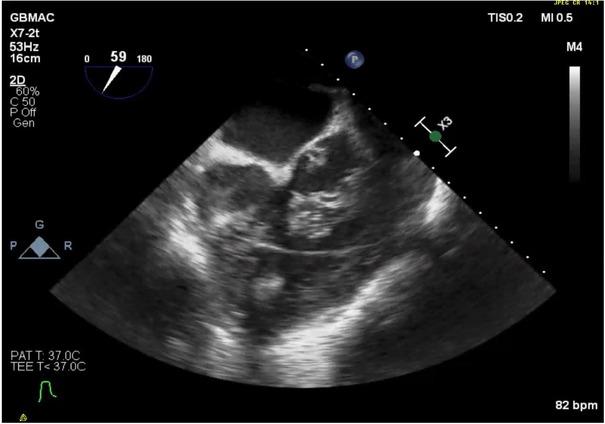

The possibility of acute myocardial infarction (MI), likely in the right coronary artery (RCA) distribution region, was considered. TEE video clips demonstrate clots located in all four chambers (Figure1; Online supplementary video 1); a massive clot in mitral position on the biplane view (Figure 2; Online supplementary video 2); and clots in both ventricles, as demonstrated on Figure 3 (Online supplementary video 3), that also showed that right ventricular outflow tract (RVOT) inflow-outflow was almost obstructed with a clot in AV.

Fig.3

Large clots in the RV outflow position